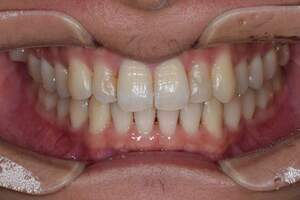

PMTC・オフィスホワイトニング

治療前

治療後

| 年齢 | 46歳・男性 |

|---|---|

| 主訴 | 着色を取りたい・歯を白くしたい |

| 治療内容 | PMTC・オフィスホワイトニング |

| 治療期間 | 90分 |

| 費用 | PMTC 5,500円 オフィスホワイトニング2回 6,600円(自費 診療) |

| リスク・副作用 | ・生活習慣(喫煙・コーヒーなど)により再度着色することがあります ・詰め物や被せ物はホワイトニングでは白くなりません ・ホワイトニングの効果は永久的なものではなく徐々に色戻りが起こります ・ホワイトニング後は歯の表面の水分量が一時的に少なくなりしみることがあります ・保険適用外の施術です |